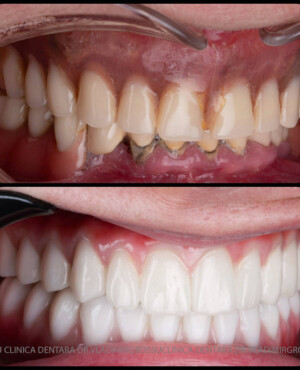

Această metodă este recomandată pacienților edentați total sau celor cu lipsuri dentare multiple. Procedura se realizează într-o singură etapă, iar pacientul primește proteza provizorie în ziua următoare intervenției. De regulă, proteza provizorie este realizată din masă plastică frezată. Suturile se îndepărtează după 5-7 zile.

La aproximativ 6 luni de la prima etapă, pacientul revine pentru protezarea definitivă. În această fază, medicul lucrează la nivelul multiunit-urilor și nu direct pe implanturi, ceea ce reduce riscurile pentru implant în etapa protetică.

Pentru pacienții cu edentație extinsă sau dinți nefuncționali, conceptele All-on-4 și All-on-6 oferă soluții fixe, moderne și eficiente, care asigură estetică, confort și funcționalitate superioară față de proteza mobilă.